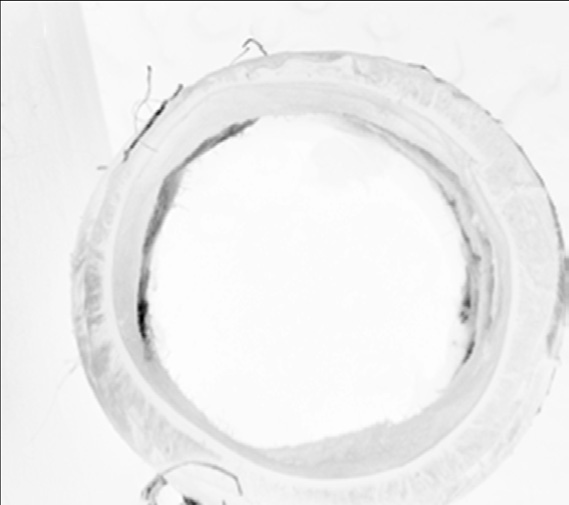

周围神经在结构上被组织成具有功能意义的区室。由胶原蛋白和弹性纤维组成的外膜基底膜包裹着神经,将其与其他组织分隔开来。在外膜基底膜内部,轴突根据其延伸的解剖区域进行分组,每组轴突被束膜包裹。轴突及其包绕的束膜膜被称为神经束[2]。神经中的神经束数量可以从一个到一百多个不等,具体取决于神经的大小和复杂性。鉴于引导再生轴突到达其适当靶点的重要性,重建束状结构是神经再生策略面临的一个挑战。

静电纺丝技术的高度可变性使得能够制造由不同尺寸和材料的纤维组成的多层系统。Panseri等人将16号旋转铜线放置在接地靶附近,通过静电纺丝技术沉积微米和纳米纤维,以制备坐骨神经管植入物。首先沉积较大的PCL纤维60秒,随后涂覆较小的PCL/PLGA纤维120秒。导管的总壁厚约为155 μm。较大PCL纤维层确保了机械稳定性和弹性,而较小的PCL/PLGA纤维则形成了紧密的外层网状结构。样品在55°C下退火24小时真空去除可能的残留溶剂,并进一步使PCL片段结晶以增加机械强度。导管在大鼠坐骨神经模型的10毫米神经缺损中进行了体内测试。受伤动物作为阴性对照。术后四个月,对照组动物的坐骨神经未发生再生。在大多数使用双层电纺管治疗的动物中,两条切断的坐骨神经束实现了功能性的重新连接。检测到髓鞘化和IV型胶原沉积与再生纤维同时出现,且未发现明显的炎症反应。神经示踪剂证实了功能性神经元连接的重建,诱发电位结果显示出大多数治疗动物的目标肌肉实现了再支配[62a]。